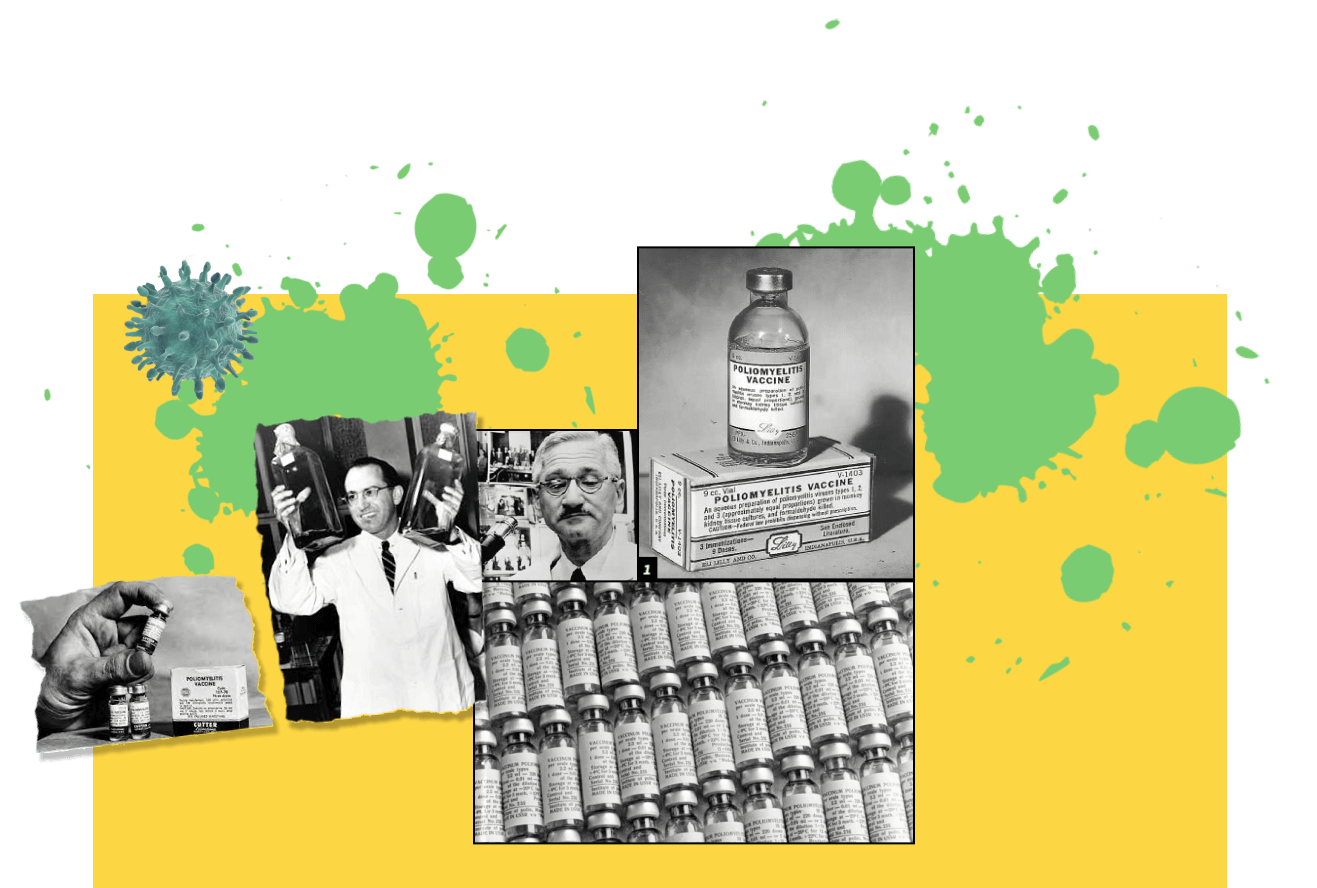

В 1796 году Дженнер провел эксперимент на человеке, вакцинировав восьмилетнего мальчика.

История создания первой вакцины

Английский врач пришел к заключению, что содержимое молодых незрелых пустул коровьей оспы, которое назвал словом «вакцина», предотвращает болезнь в случае его попадания на руки молочниц. Из этого следовал вывод о том, что искусственное заражение коровьей оспой — безвредный

и гуманный способ предотвращения натуральной оспы.

и гуманный способ предотвращения натуральной оспы.

Только в xx веке от натуральной оспы умерло

300 млн человек

Вакци́на — медицинский препарат биологического происхождения, обеспечивающий организму появление приобретённого иммунитета

к конкретному антигену

полиомиелит